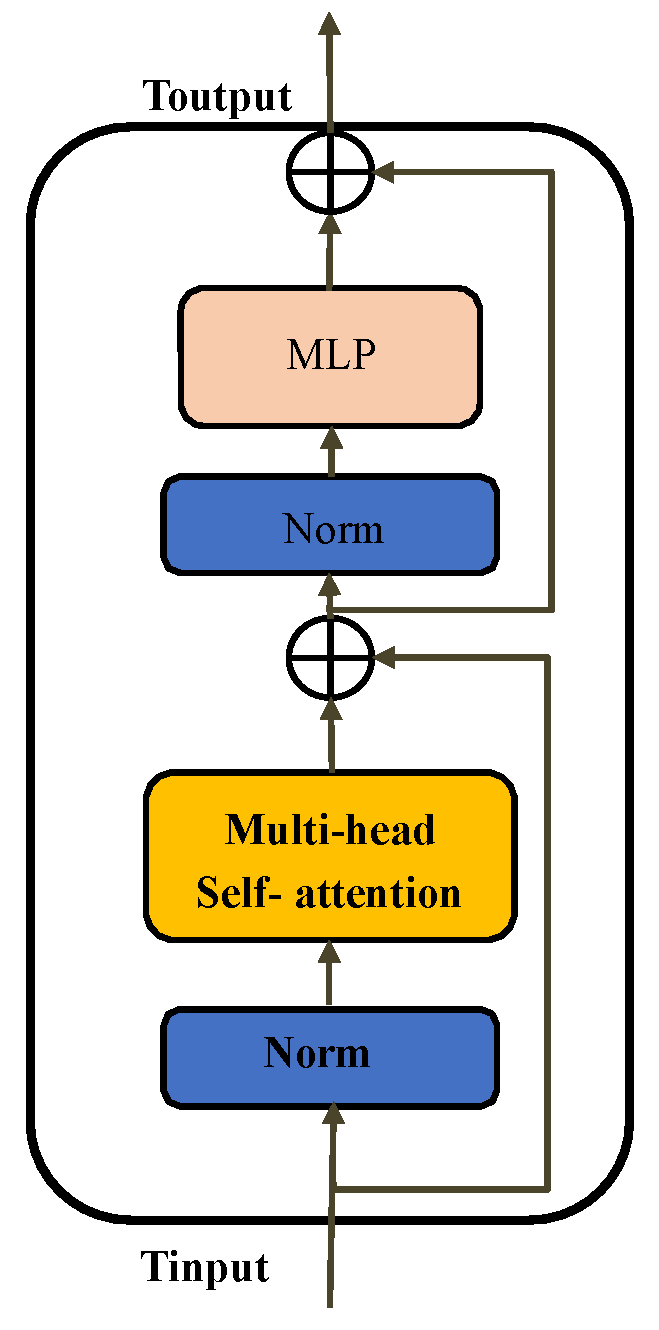

3.2. Transformer Pathway

3.3. Feature Merge Module